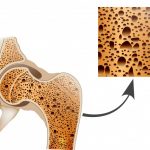

Calcium is a great way to improve your bone density, but a new study out of Spain suggests running can provide similar benefits. The findings published this week in the European Journal of Applied Physiology revealed that endurance running can be beneficial for bone health. For the study, researchers examined how long distance running affected […]